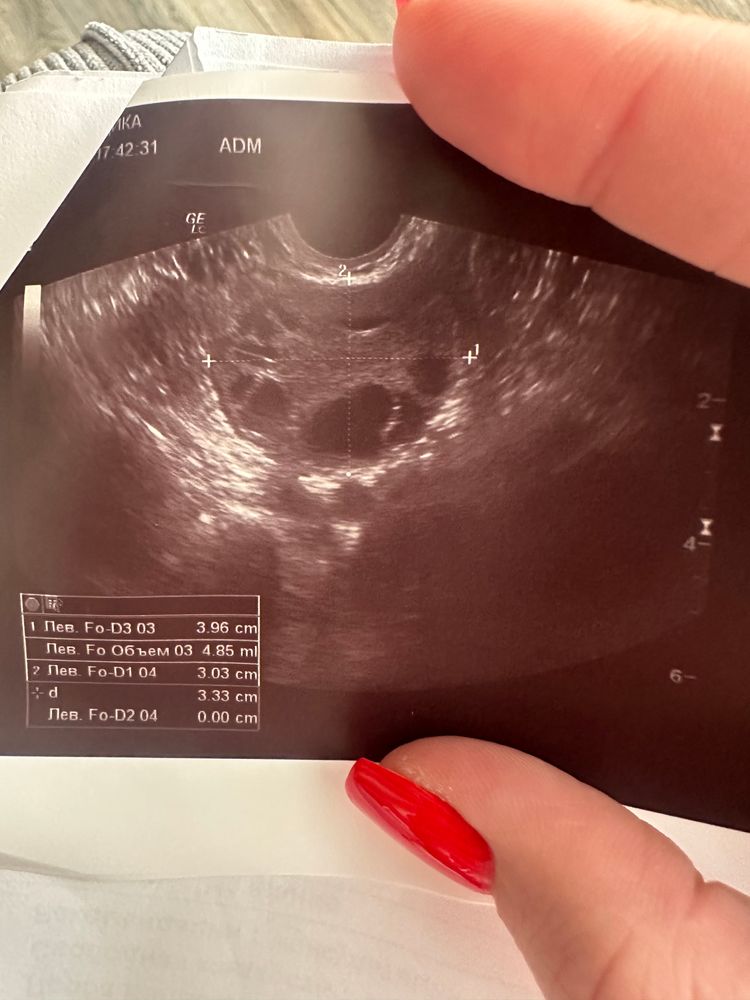

Нюша, посмотрите пожалуйста 🙏🏻 Изображение

Виктория , посмотрите пожалуйста фото Изображение

An, я вижу ДФ в момент овуляции. Яйценосный бугорок уже лопнул и ДФ сдулся, ЯК уже вышла буквально вот вот либо в процессе выхода

Виктория , 16,5 мм мало ведь думаю

Виктория , или Вы про это и говорите, что вышла Я и сдувается Ф

An, да, про это

An, если приглядеться и это не помеха экрана, то вроде ещё видно ЯК на выходе. Изображение

Узи фолликулометрия Овуляция? Дф? Или желтое тело?